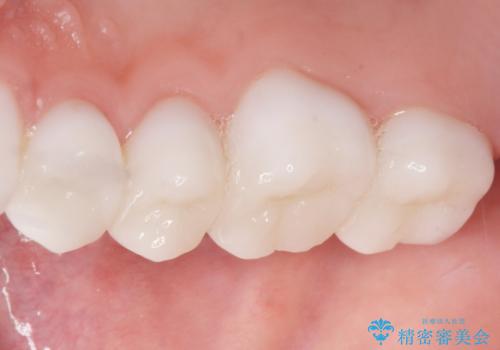

綺麗な仕上がりにご満足下さいました。

奥歯の咬み合わせも良くなったと喜んで頂けました。

患者様の理想とする韓流アイドルの写真を技工士さんに送り、最終的なクラウンの形や色をできるだけ理想に近づけられるよう努めました。

下顎はホワイトニングを行っております。

クラウンの種類:オールセラミッククラウン スタンダード